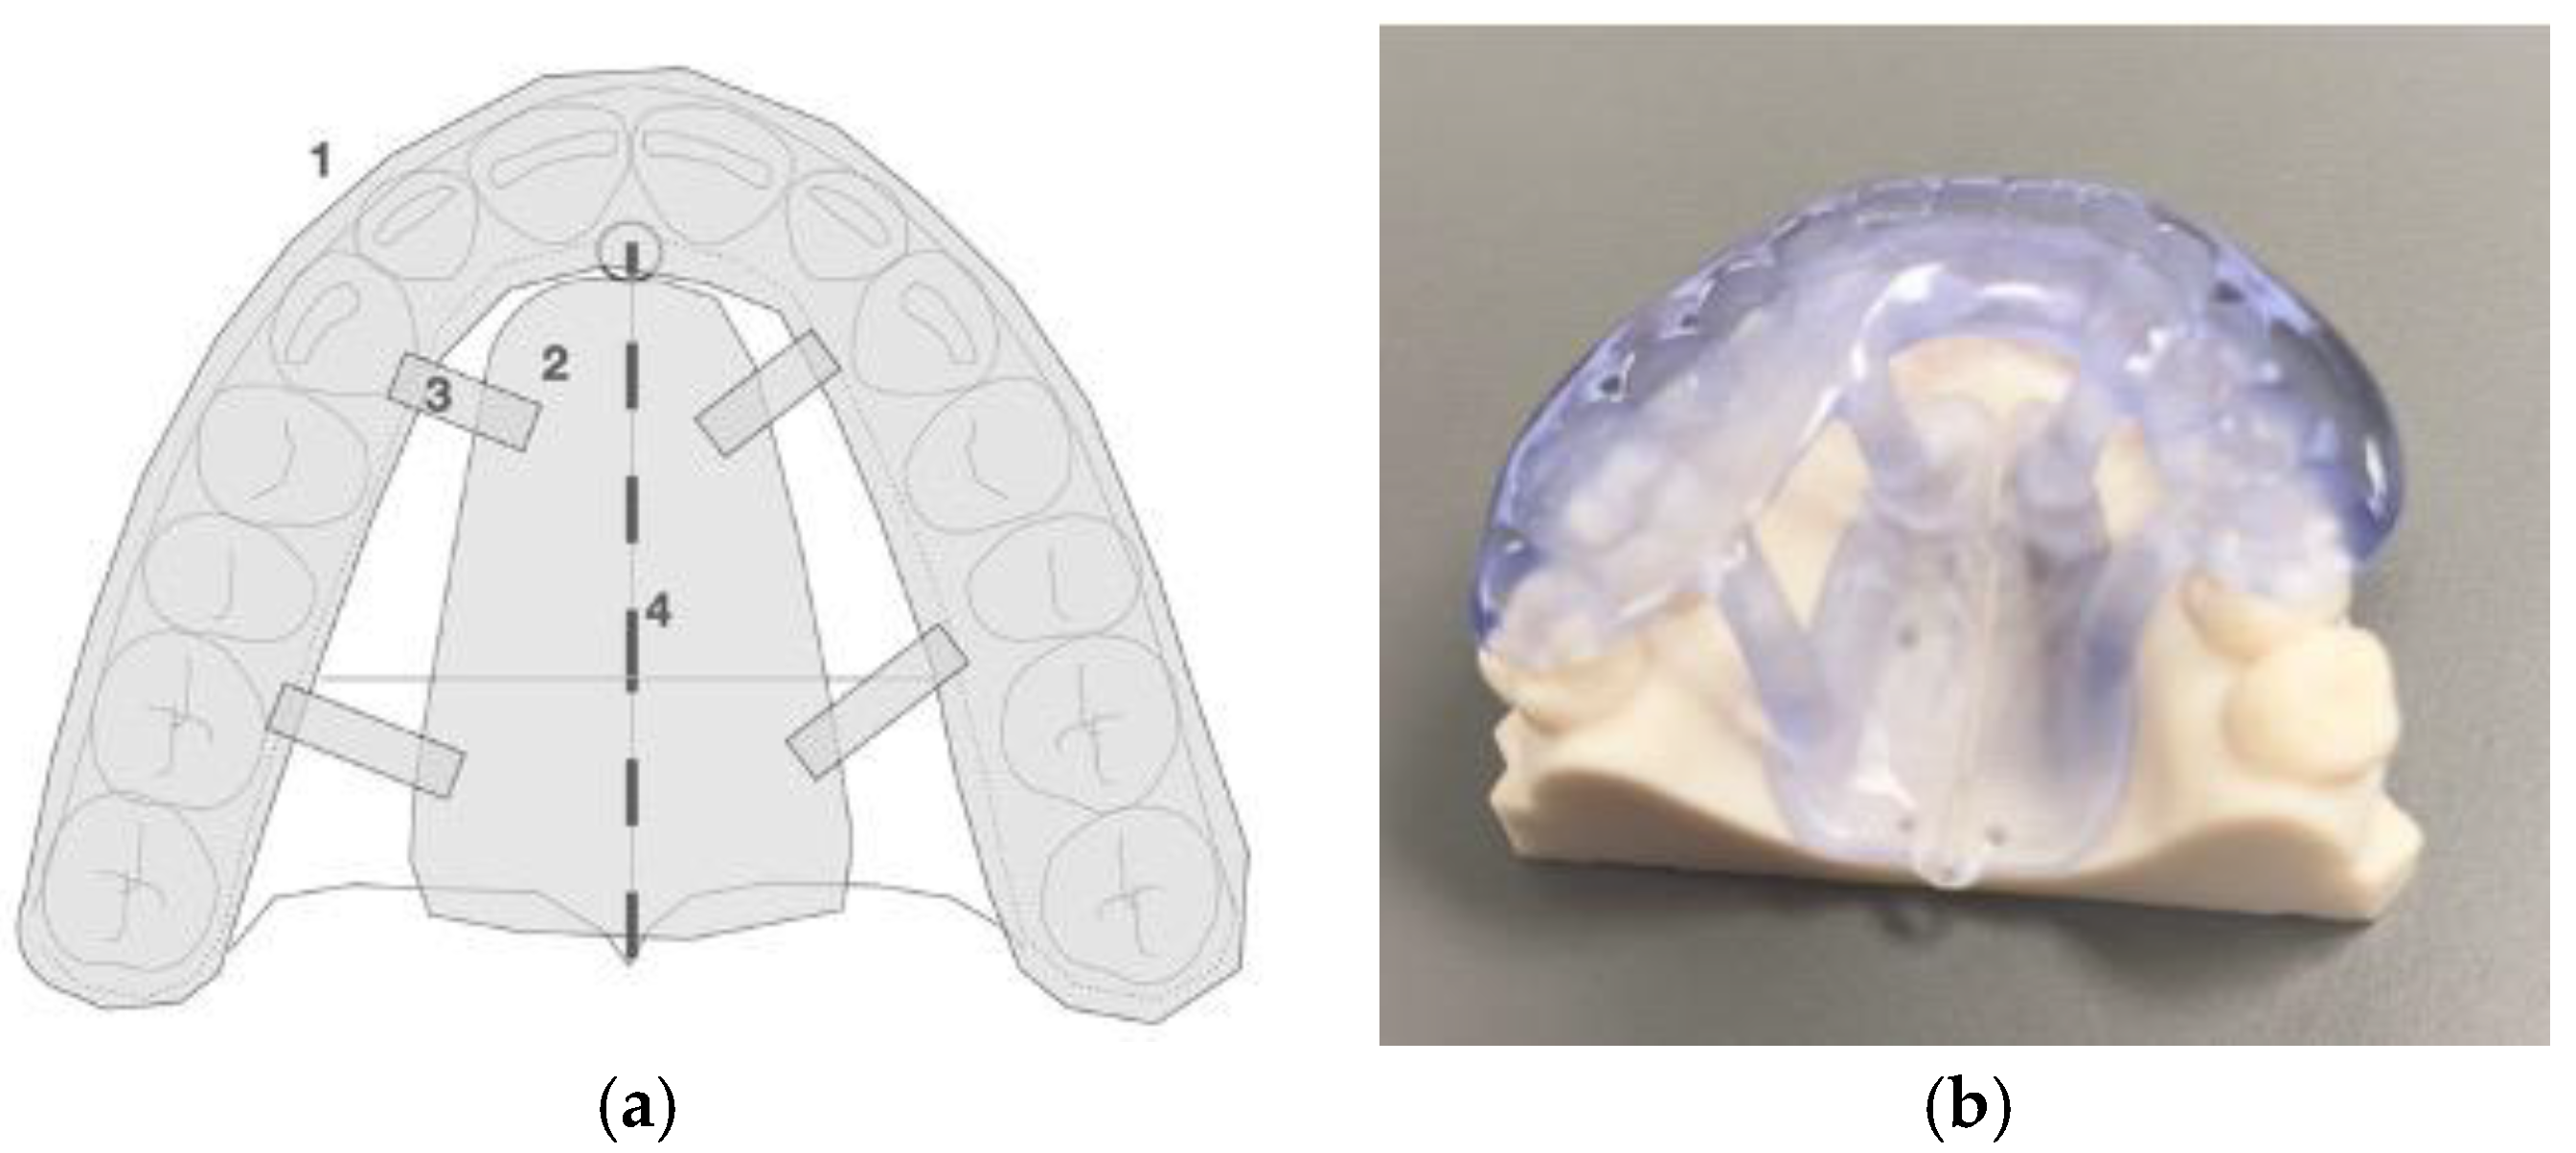

2.2. Description of the Novel Piezocorticotomy Guide for Midpalatal Skeletal Expansion

2.3. Technique of the 3D Printed Guide-Assisted Midpalatal Piezocorticotomy